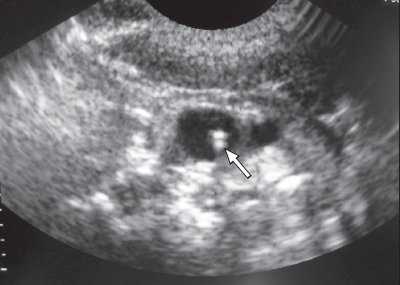

Одной из проблем при катетеризации центральных вен является корректная позиция центрального венозного катетера, при которой его конец должен находиться в полости верхней полой вены над правым предсердием. По данным отечественных и зарубежных исследователей, некорректная позиция центрального венозного катетера против тока крови встречается в 0,5-18% случаев (в 5-18% при катетеризации v. subclavia и в 0,5-5% при катетеризации v. jugularis interna). Наиболее частым вариантом некорректной позиции является расположение катетера в полости внутренней яремной вены при катетеризации одноименной подключичной вены (рис. 6). В настоящее время существует несколько методов верификации позиции центрального венозного катетера: рентгено-контроль, ЭКГ-контроль; одним из них на практике становится УЗИ для уточнения положения центрального венозного катетера (рис. 7, 8).

Рис. 7. Тот же катетер в просвете внутренней яремной вены при поперечном сканировании.